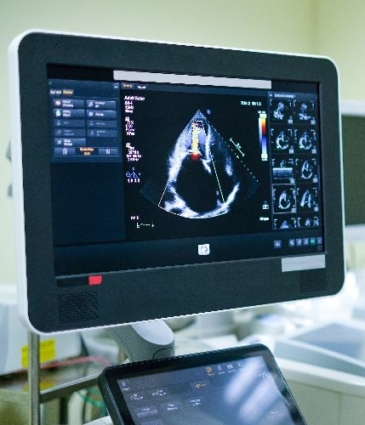

BUBBLE ECHOCARDIOGRAM BY DR SEN

A Bubble Echocardiogram is a specialist heart ultrasound used to detect a hole in the heart, such as a PFO (patent foramen ovale) or ASD (atrial septal defect). Dr Sayan Sen offers this diagnostic test at leading cardiology clinics in London.

A Bubble Echocardiogram is a targeted form of contrast echocardiography. It assesses for abnormal blood flow between the heart’s chambers – typically through a small opening like a patent foramen ovale (PFO).

During the test, a harmless saline solution mixed with tiny bubbles is injected into a vein. As the bubbles travel to the heart, ultrasound imaging tracks whether they pass from the right to the left side of the heart. This test is key in diagnosing shunts linked to stroke, migraines or breathlessness, especially in younger patients.